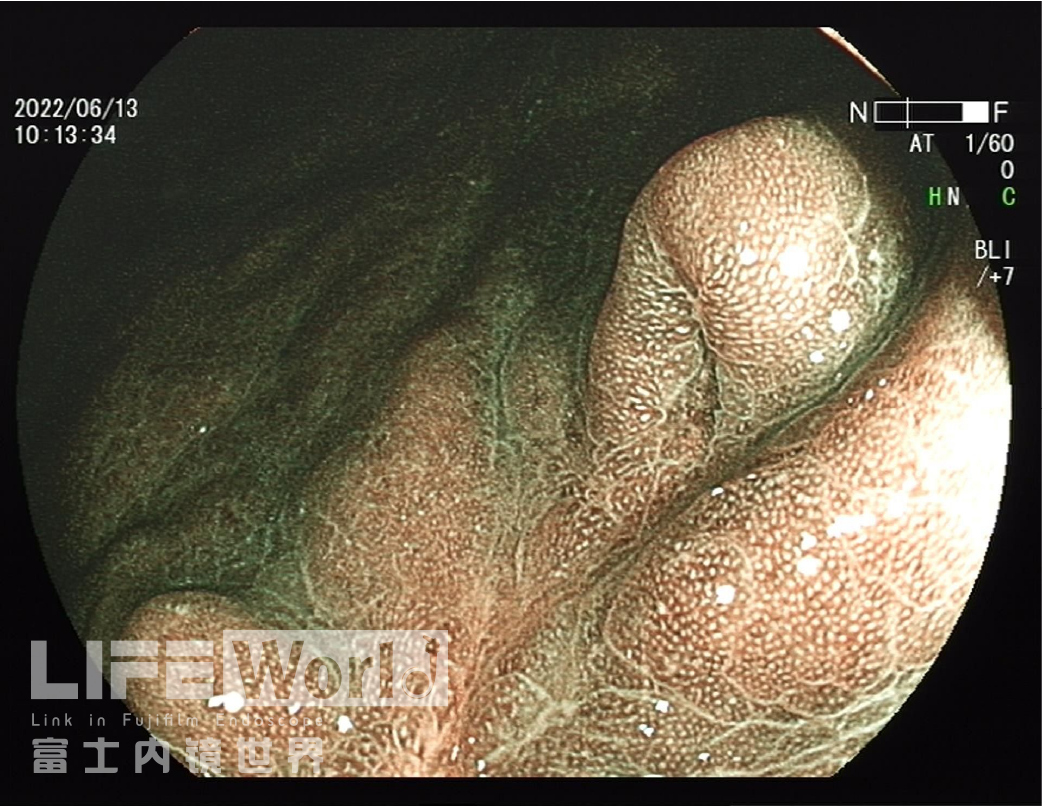

BLI模式低倍放大观察,可清晰的勾勒出病变的范围,病变的口侧端表面微结构的异型性明显,考虑为癌灶,病变的肛侧端异型性不明显,考虑为上皮内瘤变。

对考虑为癌灶的区域进行中倍放大观察:IMSP(+), IMVP(+)。

3、BLI放大下,口侧有明显的边界,有不规则的表面微结构和血管构造,考虑癌。有白色球状物,多见于分化型癌。腺体融合、血管构造不规则的树枝状,局部表面微结构显示不清,这些都支持中分化癌。